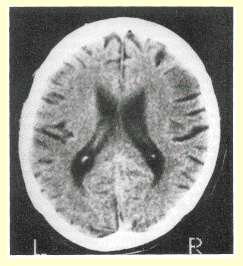

Alzheimer's disease: CT scan of brain showing cortical atrophy, widened sulci, and enlarged lateral ventricles.